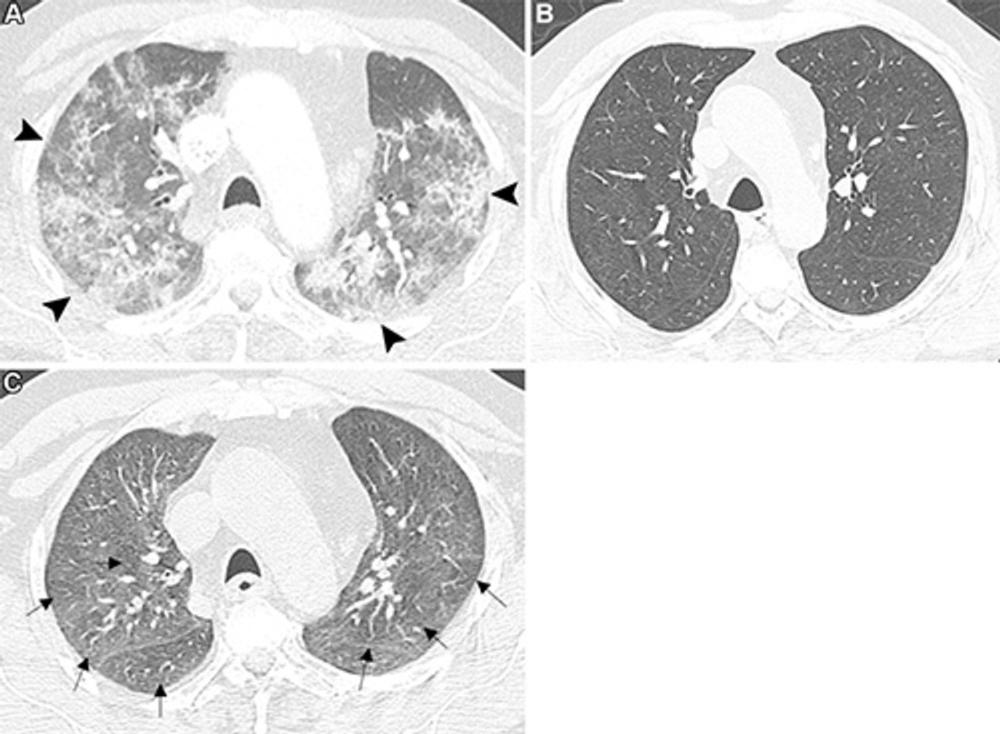

Figure 2. Axial chest CT images show air trapping following COVID-19 pneumonia in a 61-year-old male patient with persistent mild dyspnea at exertion with dry cough. (A) Contrast-enhanced image shows patchy areas of consolidation and ground-glass opacities with subpleural and peribronchovascular distribution in the upper lobes (arrowheads), consistent with COVID-19 pneumonia. (B) Full-inspiratory unenhanced image obtained 10 months later because of ongoing mild exertional dyspnea and dry cough shows complete resolution of the previous bilateral lung abnormalities. (C) Full-expiratory unenhanced image shows patchy hypodense areas of air trapping in the upper lobes (arrows). The inspiratory images show an absence of mosaic attenuation.